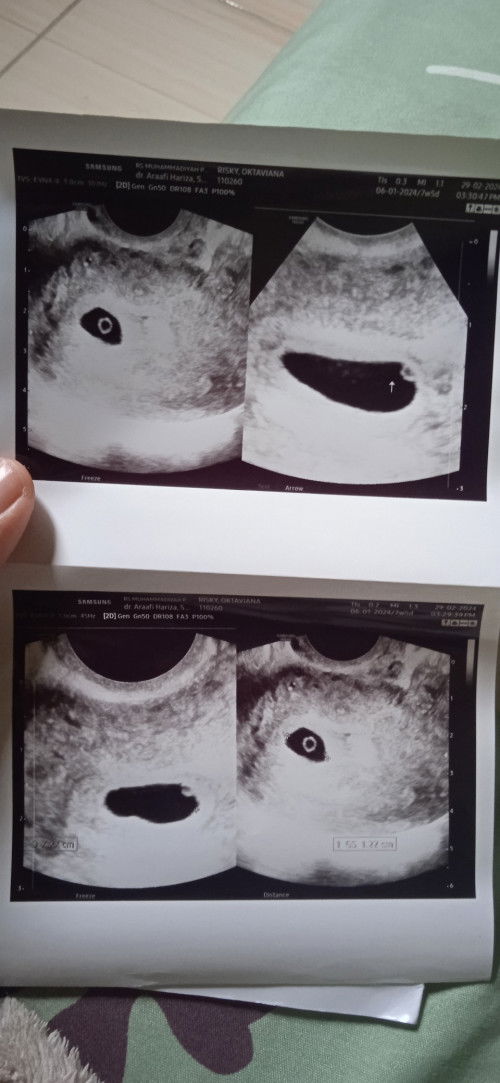

Selisih USG

Bun ada yang SMA kalo di hitung dari hpht 7minggu TPI pas diusg masih 5 Minggu an kita dokter saya salah hitung, tapi kelihatannya jga salah hitung saya jga GK tau pembuahannya kpn tiba* telat sebelah hari udah garis 2 terang aja bun

Hallo bun? ini hasilnya sama kayak waktu saya USG kemarin